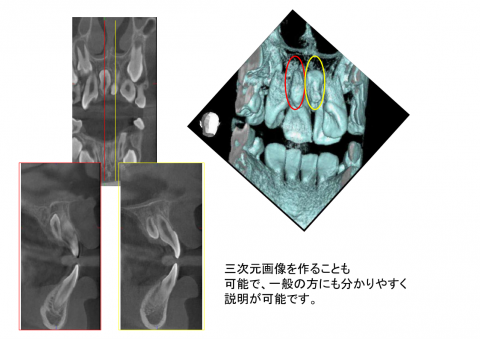

三次元画像を作ることも可能で、一般の方にも分かりやすく説明が可能です。